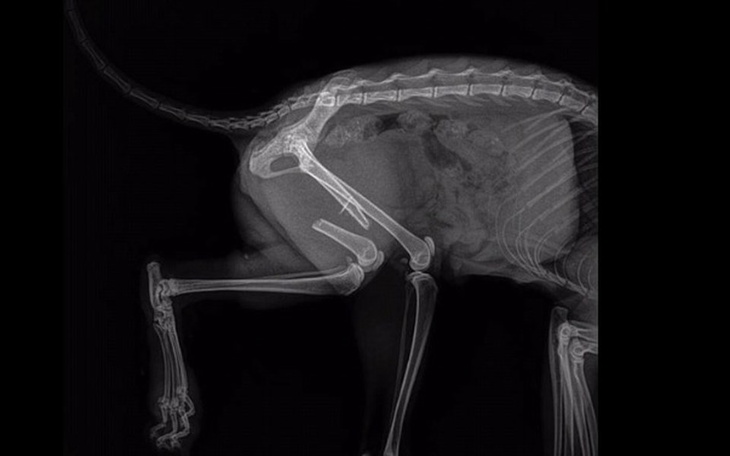

Jesteśmy już po konsultacjach. Tosia w najbliższą sobotę będzie miała zabieg usunięcia pętli z drutu. Decydujemy się na ten zabieg, gdyż pętla nie trzyma, a obecnie tylko upośledza gojenie kości w miejscu, w którym się znajduje. Gwoździe w nóżce koteczki zostają.